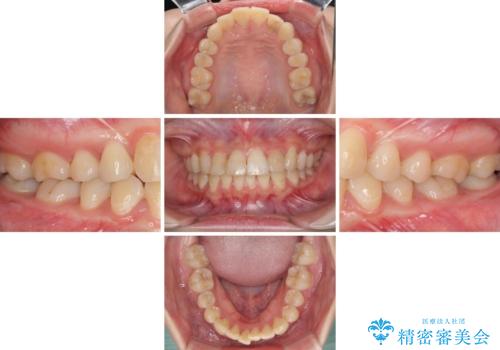

- コンポジットレジンによる治療で継ぎ接ぎだらけになってしまった前歯を綺麗にしたいとのことで来院された患者様です。

必要に応じて根管治療を行い、前歯6歯をオールセラミッククラウンで補綴することとしました。

治療途中に出産を迎えるため、下顎前歯のデコボコを部分矯正で改善し、上下前歯を綺麗に仕上げることとしました。